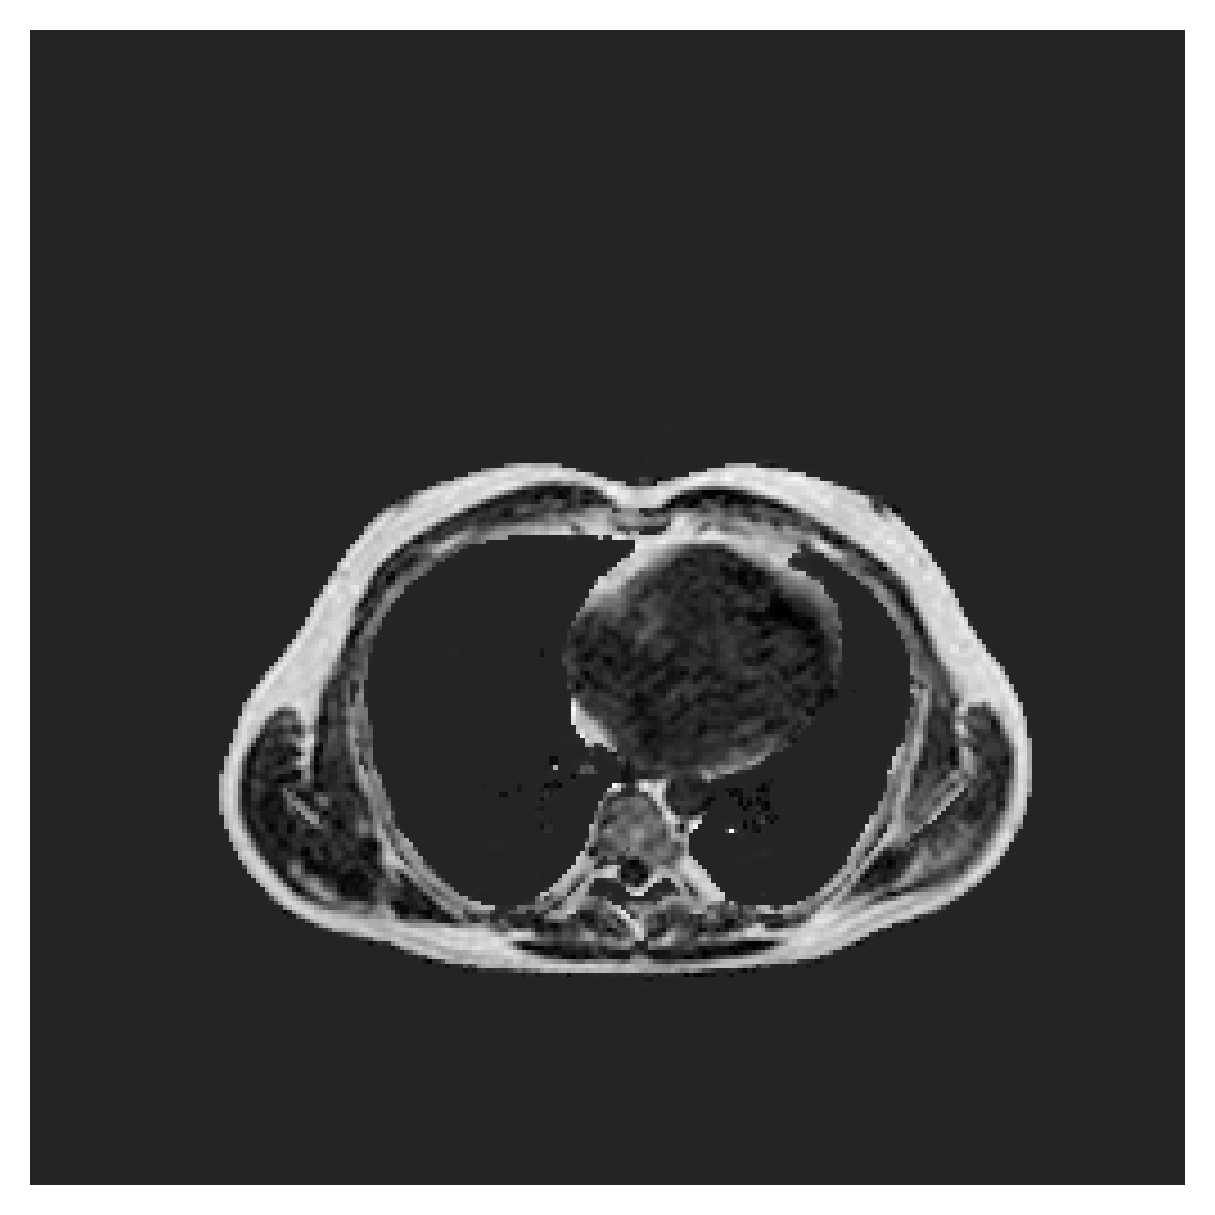

([5]) The Automated Cardiac Diagnosis Challenge (ACDC) is a public benchmark multi-class heart segmentation dataset. It contains cine-MR images of 150 patients (of which 100 are available for training and the rest 50 comprise a test set), covering healthy scans and four types of pathologies in equal amounts, with annotations for the right ventricle (RV), myocardium (Myo) and left ventricle (LV) heart structures. We split the training set randomly, using 65 subjects for training, 10 for validation and 25 as a hold-out test set. Due to the large and varying interslice gap, we work with 2D slices instead of 3D volumes directly. This includes distance map computation.

We normalize the volumes and resize the slices to pixels. As the official dataset comes with full annotations, we create a synthetic point ground truth. This is done by first randomly choosing the centers of the point annotations within the class masks, followed by filling an ellipse with axes lengths of and (in pixels) around each center. The intersections of these elliptic discs with the underlying full annotations are then used as our point ground truth. See Figure 2 for an example of the created weak annotation mask. The point annotations are created for every slice, one for each foreground object present in the slice.